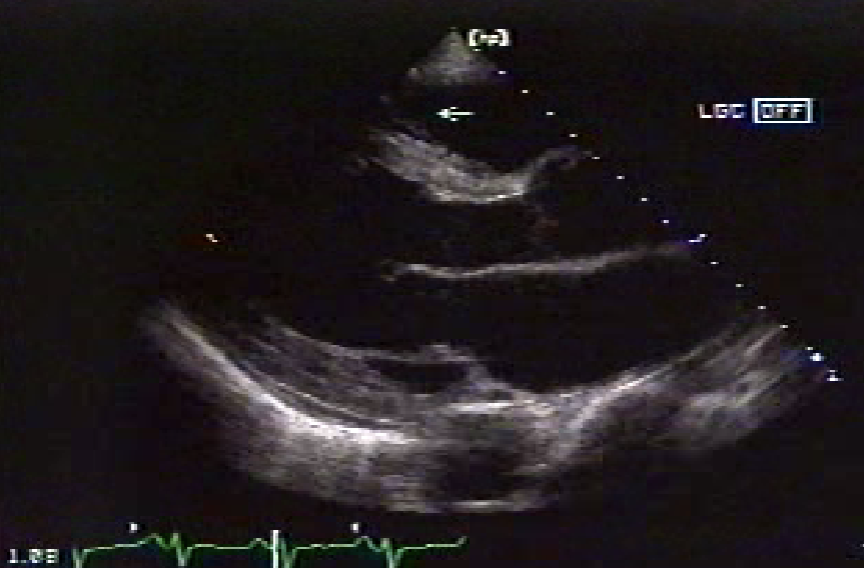

Moderator Band (Septomarginal Trabecula)

thick bundle of muscle traversing the RV

variable size

often verifies RV in fetal scanning

seen in lower 1/3

more toward apex

not always visualized

may act as a protective mechanism to resist RV overdistension